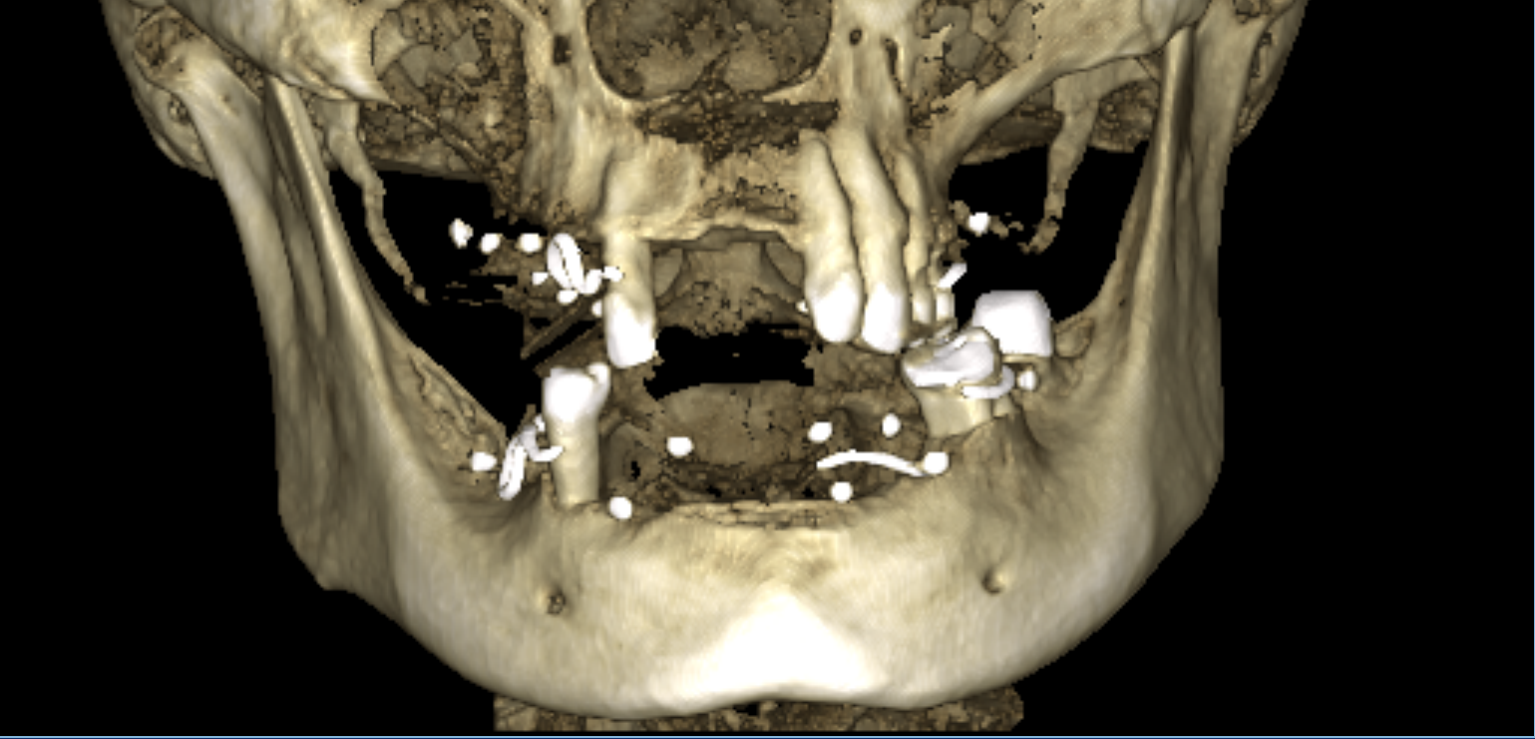

Пример комплексной реабилитации пациента конструкциями с опорой на дентальные

имплантаты при полной адентии.